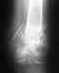

Благодарю доктора Шалина Артёма Сергеевича за то, что поставил меня на ноги после перелома шейки бедра.Диагноз: Чрезвертельный перелом культи правого бедра.Проведенyое лечение: 29.06.2017 Комбинированый закрытый интрамедуллярный остеосинтез правого бедра стержнем"ОСТЕОСИНТЕЗ" и аппаратом фнешней фиксации17.08.2017 Удаление аппарата наружной фиксации. Через неделю после травмы врачи в клинике Студенческая 12 сделали мне операцию. Чувствую себя хорошо!!! Спасибо огромное всем врачам, сёстрам, нянечкам и особенно хирургу Шалину Артёму Сергеевичу!!!